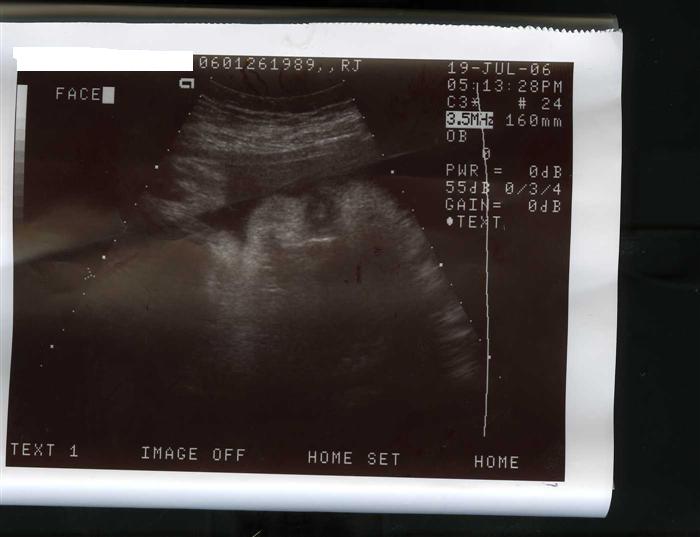

I had my first growth sono last night @ 33w3days... everything looks great... she is weighing in at 6lbs4oz I know they arent too accurate and that it can be wrong by a lb either way, I am hoping they are overestimating by a lb and not underestimating I have had a feeling this whole time that I am going early and it looks like I just might! anyway here is a picture of her chubby cheeks!

Image Attachment(s):